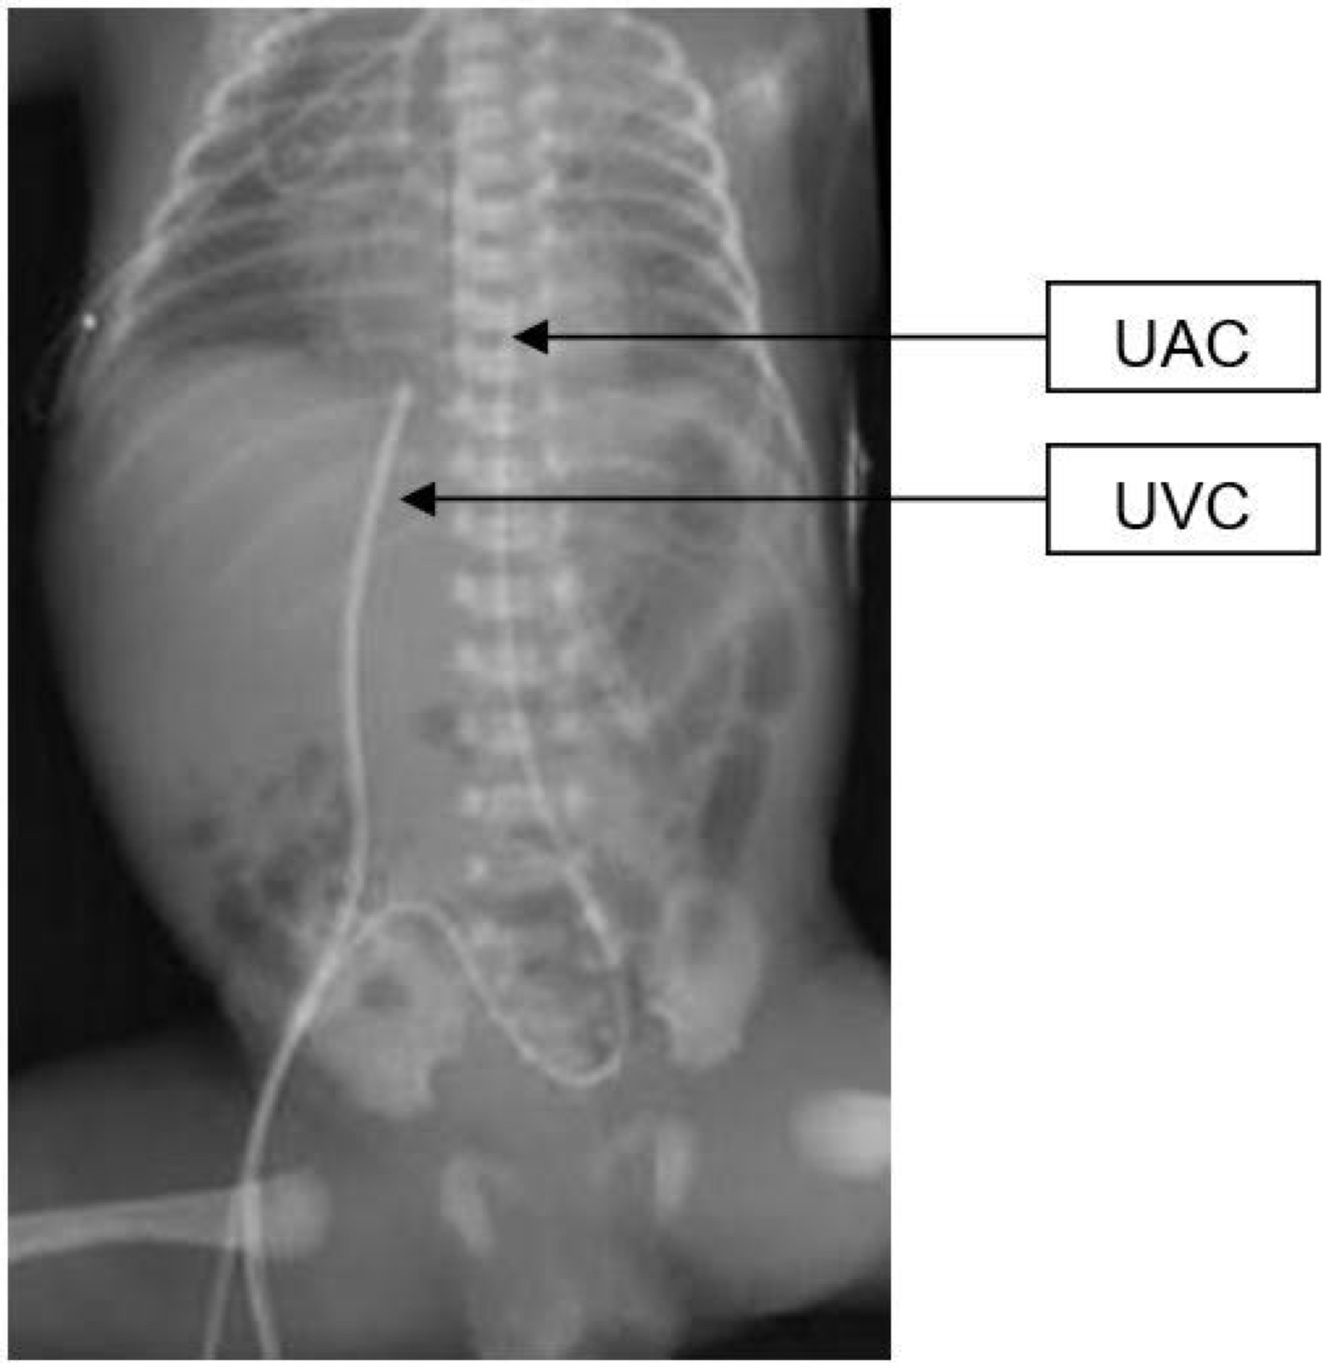

Neonates are often managed with catheters placed either in the umbilical vein and/or one of the umbilical arteries.

The tip of the UVC should be positioned at the junction of the inferior vena cava (IVC) and the right atrium (RA).

On the chest radiograph, the tip of the UVC should be at or above the level of the diaphragm.

The tip of the UAC is best positioned between the sixth and tenth thoracic vertebrae, cranial to the celiac axis.